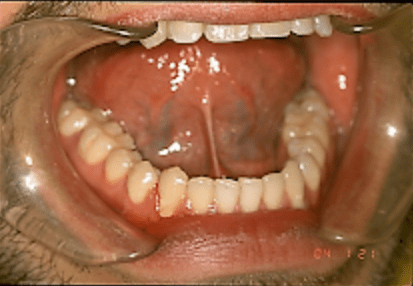

- The lower labial frenum that can be involved with a diastema between the lower central incisors and can also cause a periodontal cleft to develop.